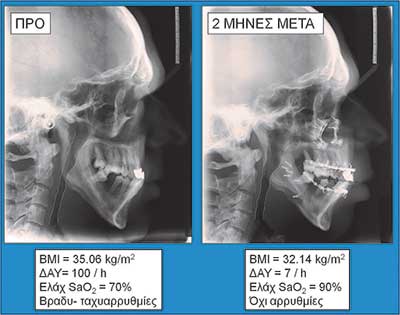

Οι εικόνες 4, 5 και 6 δείχνουν παραδείγµατα ασθενών που υποβλήθηκαν σε αµφιγναθική προώθηση. Στην εικόνα 4 πρόκειται για σύγκριση προεγχειρητικής µε 2 µήνες µετεγχειρητική πλάγια κεφαλοµετρική ακτινογραφία, όπου διακρίνεται η χοανοειδής διεύρυνση του φαρυγγικού αυλού στο οπισθοϋπερώιο και στο οπισθογλώσσιο τµήµα του. Ο συγκεκριµένος ασθενής βελτίωσε τον ∆ΑΥ από τα 100 επεισόδια / ώρα προεγχειρητικά στα 7 επεισόδια / ώρα µετεγχειρητικά, έτσι ώστε να µη χρειάζεται πλέον να κοιµάται µε τη ρινική µάσκα CPAP. Στην εικόνα 5α βλέπουµε µέση οβελιαία τοµή από υπολογιστική τοµογραφία του αεραγωγού ασθενούς µε προεγχειρητικό ∆ΑΥ 55 επεισόδια / ώρα και ελάχιστο καταγεγραµµένο κορεσµό αιµοσφαιρίνης 77%. ∆ιακρίνεται πλήρης οπισθοϋπερώια απόφραξη και πολύ σοβαρή οπισθογλώσσια στένωση. Στηνεικόνα 5β διακρίνεται ο σχεδιασµός της αµφιγναθικής προώθησης και της συµπληρωµατικής οριζόντιας γενειοτοµής στον ίδιο ασθενή. Στην εικόνα 5γπαρατίθεται η σύγκριση του εµβαδού διατοµής του φαρυγγικού αυλού αυτού του ασθενούς οπισθοϋπερώια και οπισθογλώσσια πριν και 1 έτος µετά την επέµβαση. Είναι εµφανέστατη η αύξηση των διαστάσεων του αεραγωγού. Οι εικόνες 6α και 6β αποτελούν πλάγιες και κατά µέτωπο τρισδιάστατες απεικονίσεις αεραγωγού ασθενούς πάσχοντος από βαρύτατο ΣΑΑΥ προ και µετά την αµφιγναθική προώθηση.

Εικόνα 4